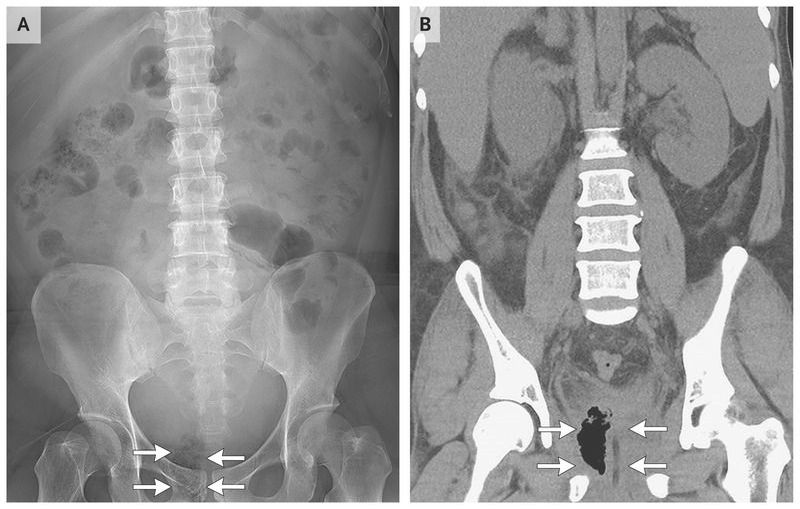

A 42-year-old man with diabetes presented to the emergency department with severe dysuria and incontinence, which he had had for several days. Laboratory studies were notable for pyuria on urinalysis, leukocytosis (a white-cell count of 10,820 per cubic millimeter), elevated C-reactive protein levels (134.1 mg per liter), hyperglycemia (glucose level, 900 mg per deciliter [50 mmol per liter]), and an elevated level of glycated hemoglobin (11.4%). Radiography of the kidney, ureter, and bladder showed an atypical focus of gas accumulation behind the right pubic ramus (Panel A, arrows). Subsequent computed tomography (CT) of the abdomen revealed emphysematous prostatitis of the right prostate lobe (Panel B, arrows). A Foley catheter was placed, and CT-guided percutaneous drainage of the prostate was performed. Broad-spectrum antibiotics and intravenous fluid therapy were initiated, and strict blood sugar control was implemented with an insulin drip. Urine and blood cultures grew Klebsiella pneumoniae. The patient remained in the hospital for 1 month and was treated for infection, sepsis, poor control of blood sugar levels, and acute kidney injury. His condition gradually improved, and he was discharged home. Emphysematous prostatitis is a rare sequela of complicated urinary tract infection and is more commonly found in patients with immunosuppression, diabetes mellitus with poor glycemic control, liver cirrhosis, alcoholism, or recent urethral instrumentation. The most common pathogen in patients with diabetes, as in this case,